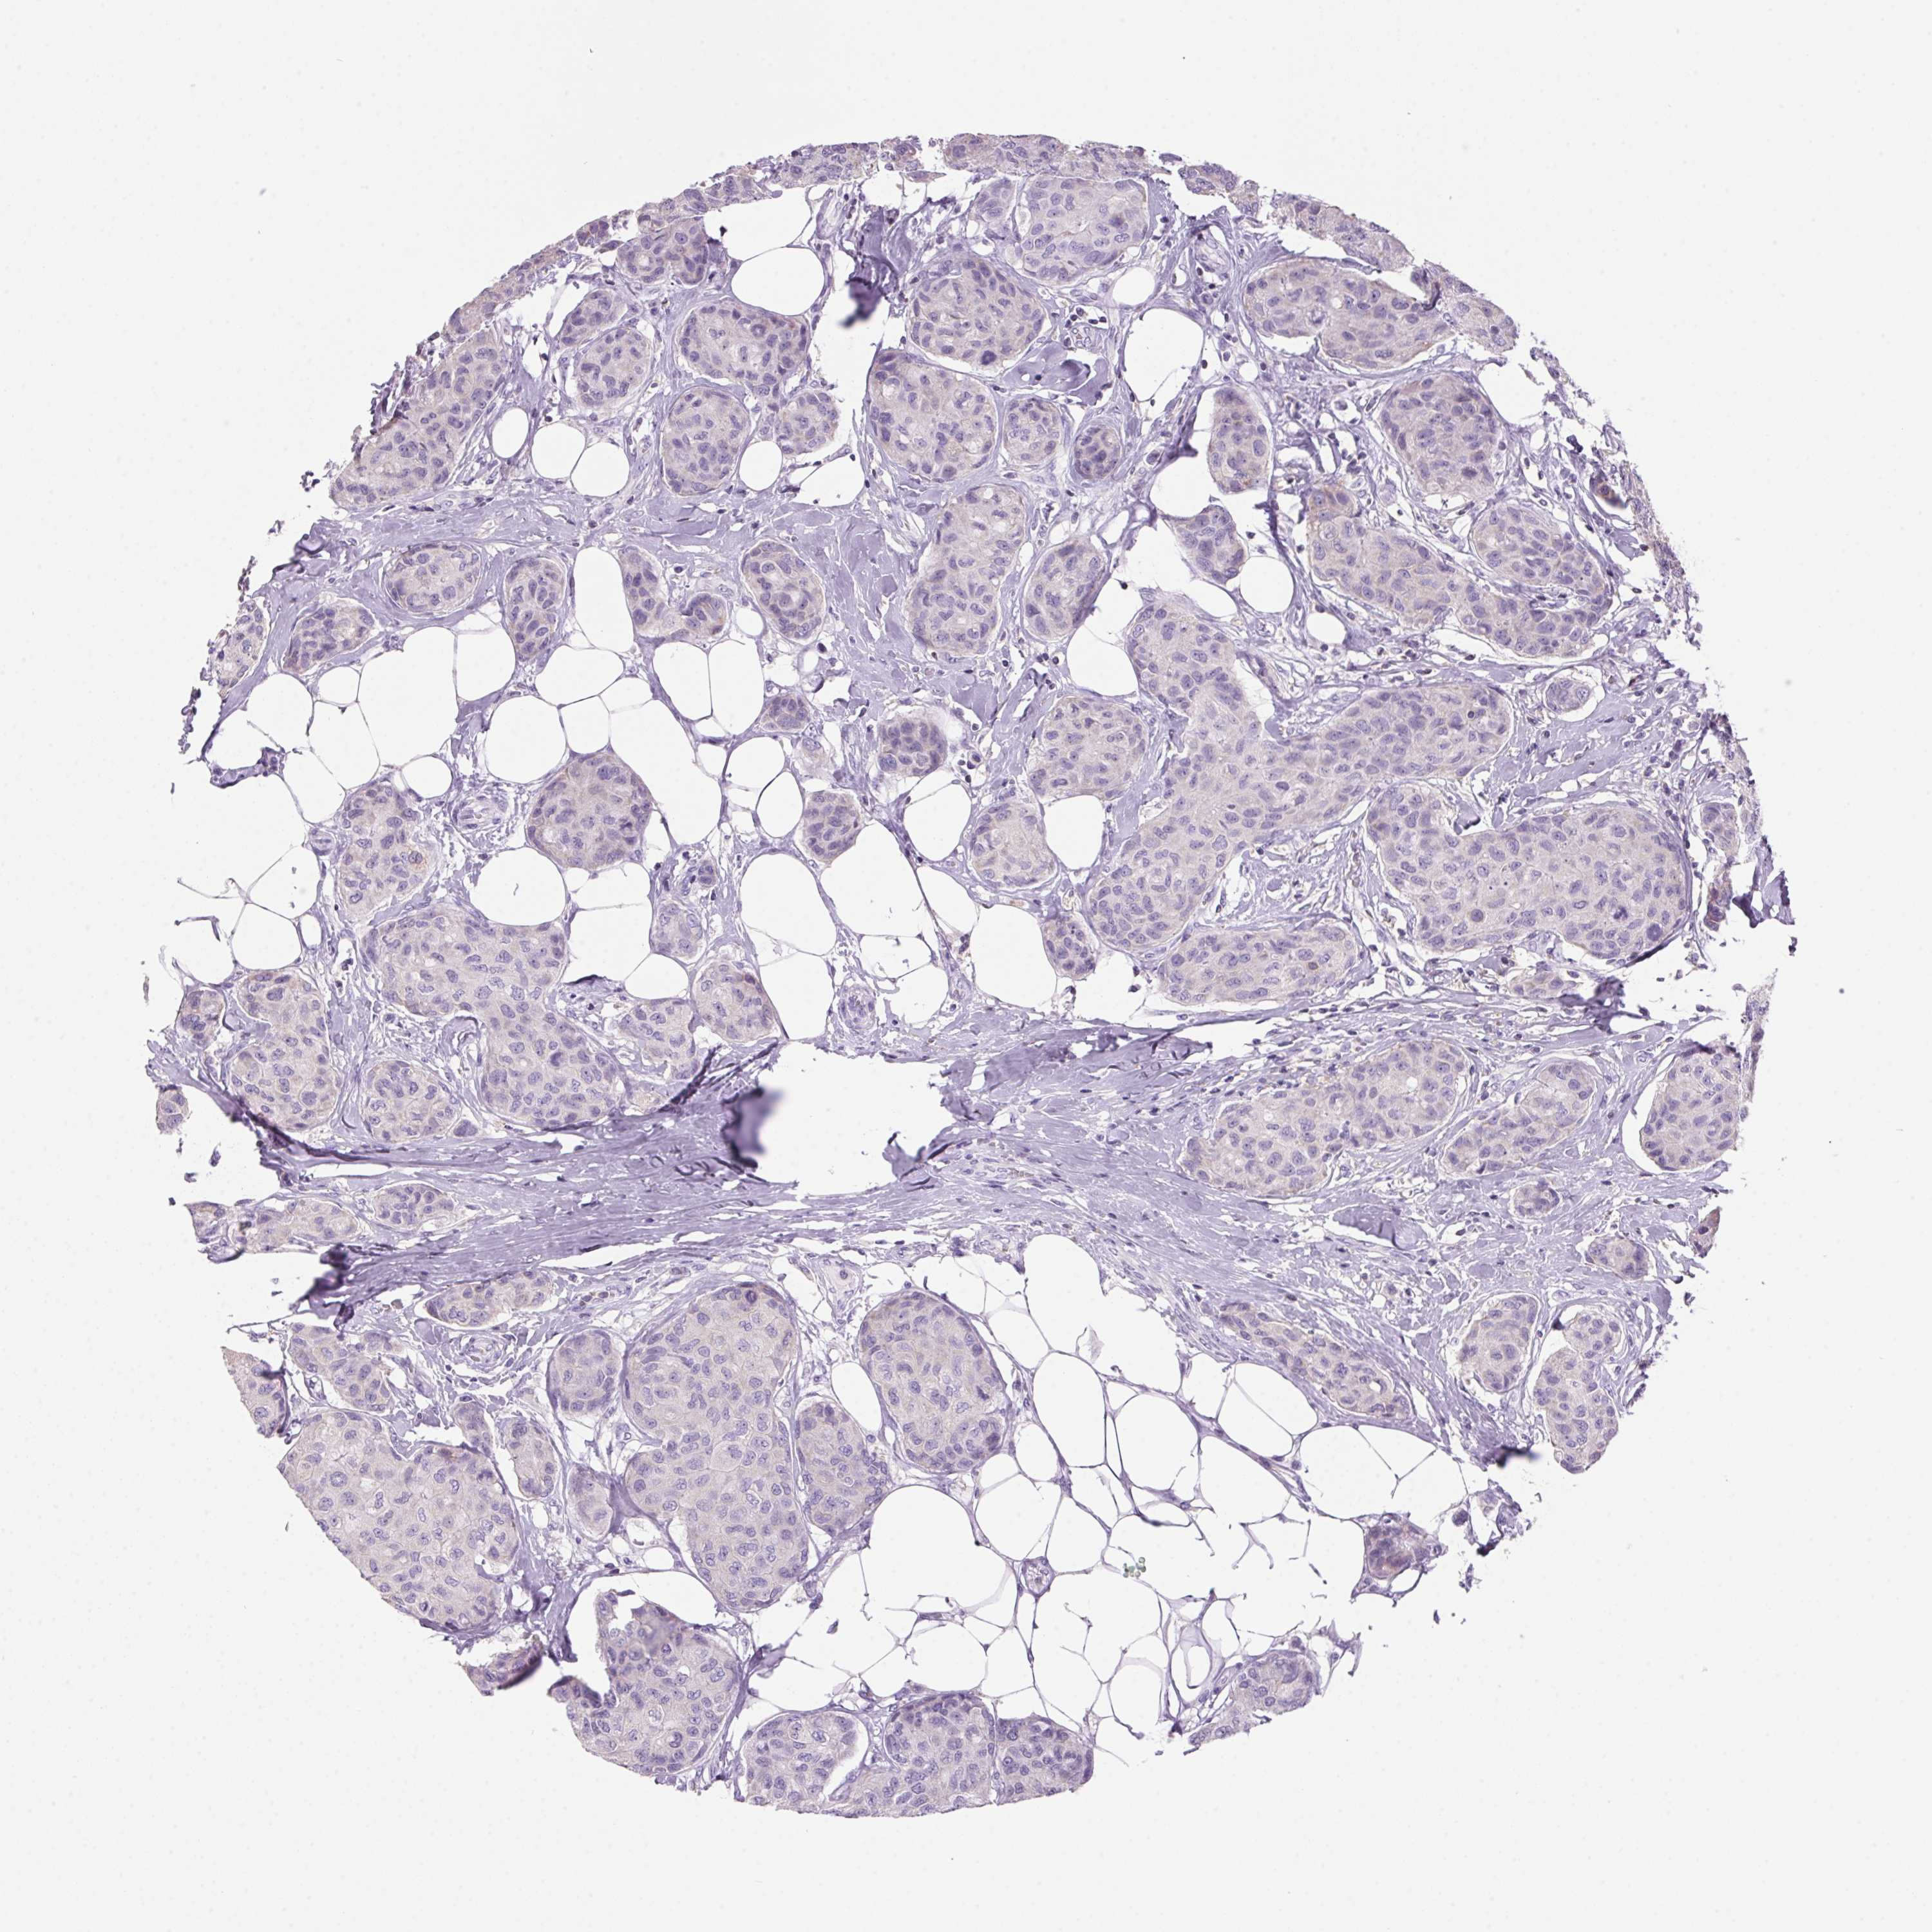

CANCER BREAST CANCER Show tissue menu

BRCA TCGA BRCA VALIDATION PROTEIN EXPRESSION

ANTIBODIES

AND

VALIDATION